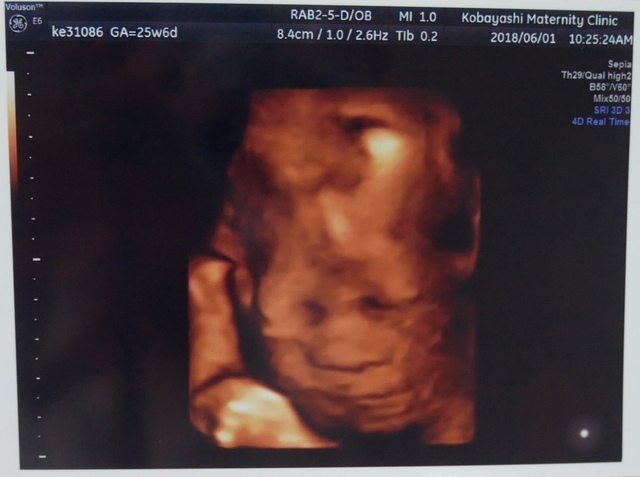

25週0日(25w0d・男の子)|まぁりん さん(31歳)

エコー写真撮影時のエピソード:

初めて顔の様子がハッキリわかった4Dエコーです!それまでなかなか4Dエコーをしてもらえず、ずっと顔が見たいと思っていました。里帰り先の産婦人科で撮っていただいたものです。旦那もこのエコー写真を見てとても喜んでいました。

私は4回の流産を経てやっとここまできたので、エコー写真をもらうたびにうれしくてたまりません!これからも大切に育てていきます。大きくなぁれ!